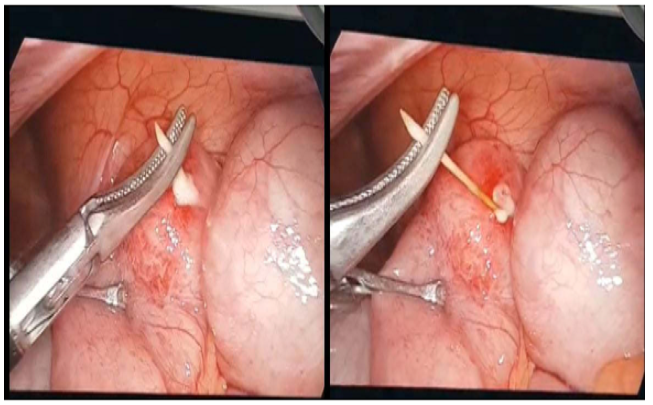

Quá trình nội soi thăm dò ổ bụng xác định dị vật giống đầu nhọn của chiếc tăm tre dài khoảng 2,5 cm nằm ở cuối ruột non (đoạn hồi tràng sát manh tràng) đâm xuyên thủng thành ruột.

Ekip phẫu thuật do Bác sĩ CKI Nguyễn Thái Bình – Phó Trưởng Khoa Ngoại, Bệnh viện Bãi Cháy đã tiến hành gắp thành công chiếc tăm tre ra khỏi lòng ruột non an toàn, khâu lỗ thủng hồi tràng, lau rửa và đặt dẫn lưu ổ bụng. Sau 3 ngày trẻ không còn đau bụng, trung đại tiện tốt, sức khỏe ổn định.